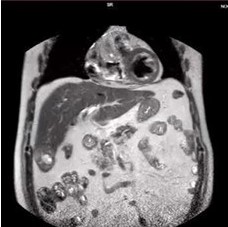

Reportamos el caso de un paciente masculino de 65 años de edad quien consultó por control. Con antecedente de carcinoma de células claras de riñón izquierdo estadio II ameritó nefrectomía radical izquierda y adenocarcinoma de próstata Gleason 9 avanzado oligometastásico, recibió tratamiento con bicalutimada, zoladex y abiraterona acompañado de radioterapia 39 ciclos; hábito OH acentuado, durante la consulta se le evidencia mediante ecografía abdominal lesión ocupante de espacio de segmento V hepático. Fue estudiado con tomografía con protocolo hepático donde se evidencia imagen redondeada de 4,7 cm, que presenta captación discreta heterogénea periférica en fase arterial, lo que sugiere área de necrosis central y un wash out lento en fase de eliminación, dicha lesión está ubicada en el segmento V y se encuentra en íntima relación con los músculos de la pared abdominal anterior ( Figura 1 y 2), Fibroscan en el cual no se evidencia cirrosis hepática, sin embargo, en vista del tamaño del tumor y antecedentes del paciente se decide realizar resonancia magnética nuclear (RMN), en la cual se evidencia lesión redondeada, bien delimitada, heterogénea que mide 5 cm x 4,5 cm x 4,2 cm en lóbulo hepático derecho segmento V con un volumen aproximado de 50 cm3 (Figura 3 y 4), pruebas de funcionalismo hepático alteradas AST 301U/l, ALT 206U/l, alfafetoproteína 244,10 ng/mL, antígeno carcinoembrionario 2,23 ng/mL, Ca 19-9 1,00 U/mL, con CT PET del año anterior negativo, por lo cual se decide realización de intervención quirúrgica con sospecha diagnóstica de carcinoma hepatocelular.